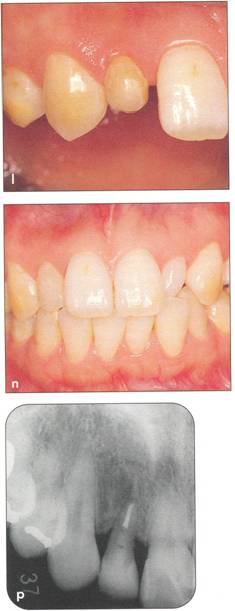

Fi 545e45f gs 5-2b and 5-2c Preoperative view of the maxillary and mandibular arches. |

Fi 545e45f gs 5-2f and 5-29 Preoperative view of the donor tooth. |

Fi 545e45f g 5-2h Extracted donor tooth. This tooth seems to be at developmental stage 6. |

Fi 545e45f g 5-2i The recipient site right before transplant procedure (2 weeks after extraction of the first molar). |

Fi 545e45f g 5-2j After suturing of the gingival flap and fixation of the donor tooth using sutures. |

Fi 545e45f g 5-2k After transplantation. |

Fi 545e45f g 5-21 Two months after transplantation. |

Fi 545e45f g 5-2m Two months after transplantation. In a developing tooth, pulpal healing is expected. One must, however, carefully watch for signs of resorption or development of bony lesions indicating pulp necrosis. |

Fi 545e45f g 5-2n Eight months after transplantation. Obliteration of the pulp canal from the apex has begun, indicating pulpal vitality. |

Fi 545e45f g 5-20 Two years 5 months after trans. plantation. Total obliteration of the pulp canal has occurred, which is a normal outcome. |

Fi 545e45f gs 5-2p and 5-2q Two years 5 months after transplantation. The donor tooth is restored with composite resin. |